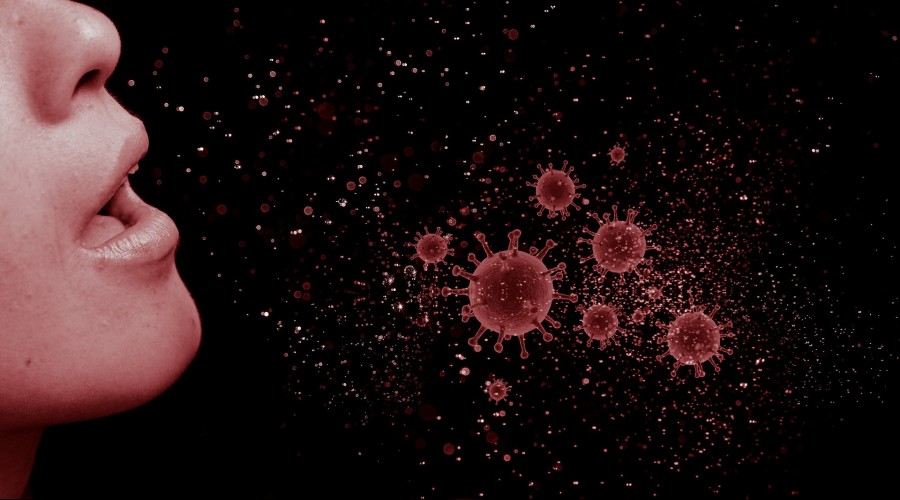

Cep telefonu, kapı kolu, merdiven korkuluğu gibi birçok yerde olabilen koronavirüse temas eden alerjik biri; elini daha sık gözüne ve burnuna götürecektir. Bunun sonucu olarak da; koronavirüs hastalığına yakalanma riski daha fazla olacaktır. Aynı zamanda koronavirüs taşıyan birisi de, sık hapşırma ve fazla burun akıntısı olması nedeniyle de etrafa daha fazla virüs bulaştıracaktır.

Sonuç olarak koronavirüs; alerjisi olanlara daha kolay bulaşabilir ve alerjisi olan hastalar etrafına da daha fazla bulaştırabilir. Bu nedenle de; polenlere karşı alerjik nezlesi olanların dış ortamda bulunmaması, ellerin daha sık yıkaması ve maske takması, mümkünse burun ve gözünü elinin dış kısmı ile silmesi çok faydalı olacaktır.

Cep telefonu, kapı kolu, merdiven korkuluğu gibi birçok yerde olabilen koronavirüse temas eden alerjik biri; elini daha sık gözüne ve burnuna götürecektir. Bunun sonucu olarak da; koronavirüs hastalığına yakalanma riski daha fazla olacaktır. Aynı zamanda koronavirüs taşıyan birisi de, sık hapşırma ve fazla burun akıntısı olması nedeniyle de etrafa daha fazla virüs bulaştıracaktır.

Sonuç olarak koronavirüs; alerjisi olanlara daha kolay bulaşabilir ve alerjisi olan hastalar etrafına da daha fazla bulaştırabilir. Bu nedenle de; polenlere karşı alerjik nezlesi olanların dış ortamda bulunmaması, ellerin daha sık yıkaması ve maske takması, mümkünse burun ve gözünü elinin dış kısmı ile silmesi çok faydalı olacaktır.